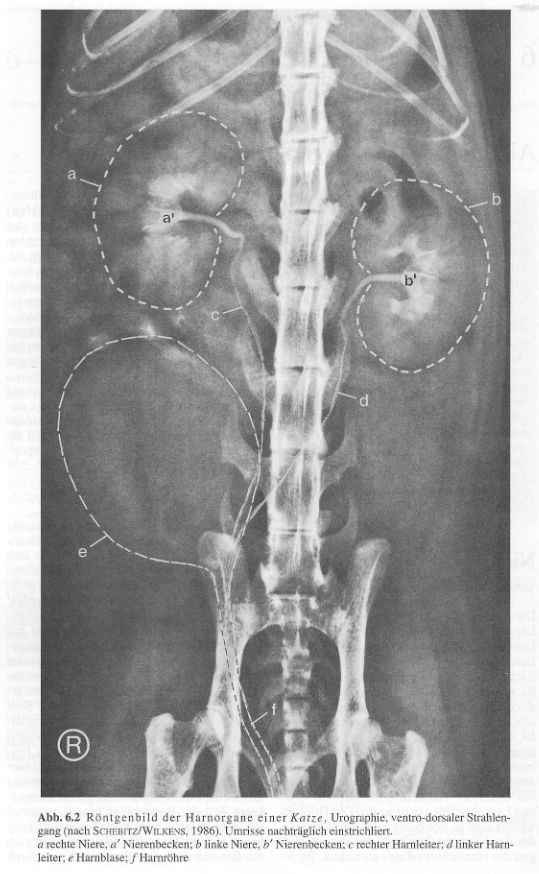

bei der Katze ist ein besonderes, kapsuläres Venennetz vorhanden, in das peripher in der Nierenrinde verlaufende Vv. interlobulares münden, es steht mit dem übrigen Venensystem der Niere nicht in Verbindung, 3 - 5 größere Vv. capsulares verlaufen auf jeder Seite Hiluswärts zur Nierenvene; sie sind in seichte Furchen eingebettet und verleihen der Katzenniere ihr typisches Aussehen;